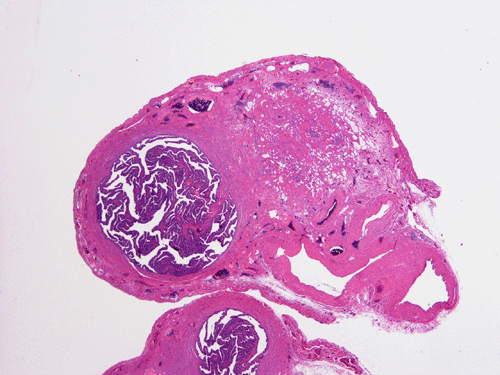

On scanning magnification, there is a round lesion in tissue around the fallopian tube (arrows in Panel A). The lesion does not invade into the tube nor distort or compress the tube. The cross sectional dimension is about the same diameter of the fallopian tube. On low and medium magnification, the lesion is composed of a collection of small microcysts intermingled with the smooth muscle bundles of the wall of the fallopian tube (Panel B and C). On higher magnification, the cyst or gland like spaces are lined by epithelioid to spindle cells with bland nuclei and an abundant amount of amphophilic cytoplasm (Panel D and E). The spindle cells are positive for calretinin, cytokeratin 5/6, and inhibin (Panel F, G, and H).

Macroscopically, ademonatoid tumors are well-circumscribed nodules with a gray-white cut surface. With the mesothelial origin, it would not be surprised that they are typically found in a subserosal location.

Histologically, the salient feature is small, microcystic or gland-like cystic spaces lined by flattened cells. Some of the tumor cells may arrange in cords and tubules.  Hyaluronic acid rich material that can be easily demonstrated by Alcian blue stain are present in the small glands and cysts. The tumor cells are medium in size and contain moderate to abundant amphophilic to eosinophilic cytoplasm. Prominent cytoplasmic vacuoles that suggest signet ring cells may be present. This is an important feature to know in order not to confuse these tumors with primary and metastatic carcinomas particularly when the specimen is obtained from the ovary. Although these tumor appears well-circumscribed on gross examination, these tumor appears infiltrative on microscopically and should not be confused with adenocarcinoma. The key to avoid this pitfall is that adenomatoid tumor have bland nuclear feature and no mitotic figures. Infaction can occur in adenomatoid tumor.